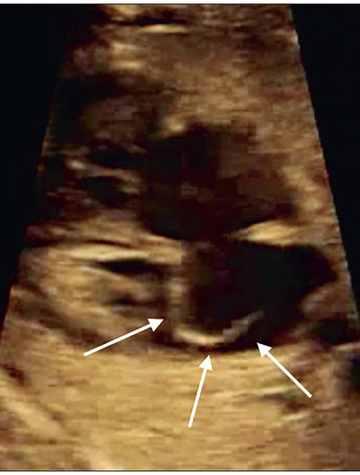

Coarctation aortique

La coarctation de l’aorte correspond à un rétrécissement de l’aorte, le plus généralement situé au niveau de l’isthme (entre le départ de l’artère sous-clavière gauche et le raccordement avec le canal artériel). Néanmoins dans un certain nombre de cas, la portion d’aorte rétrécie peut être plus importante. La prévalence de cette anomalie est estimée entre 5 et 8 % des fœtus porteurs d’une cardiopathie(1), soit 3 à 5 cas/10 000(2). il faut noter un important taux de récurrence [...]